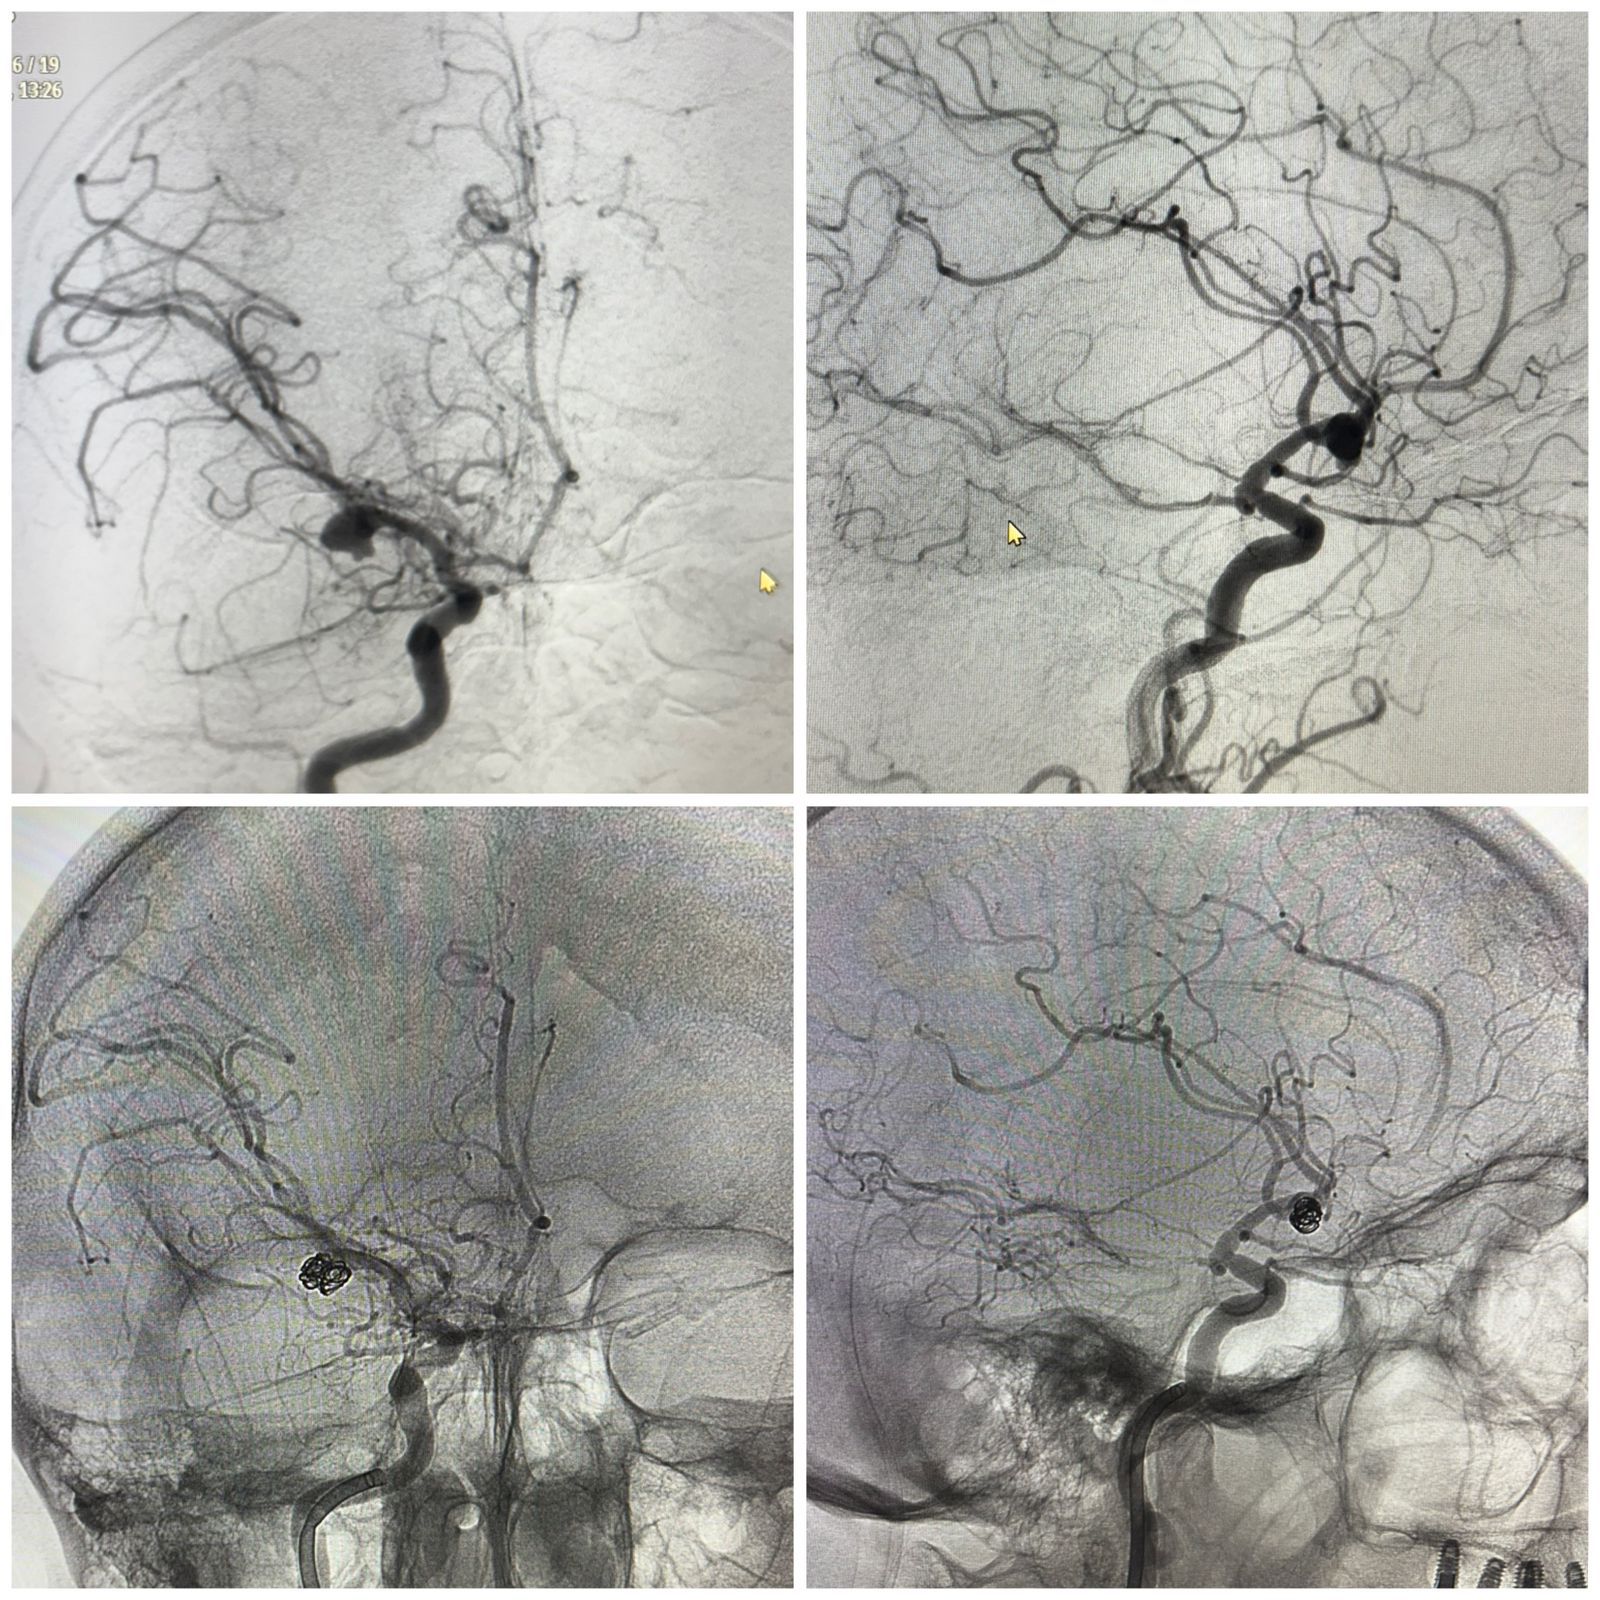

Mundaı oqıǵalardyń basym bóligi naýqas tipti aýrýhanaǵa jetpeı jatyp, qaıǵyly aıaqtalady. Alaıda bul joly ár mınýt sheshýshi ról atqarǵan. Pasıentti mýltıdıssıplınarlyq top-nevrolog, reanımatolog, neırohırýrgter men anestezıolog mamandar birlesip qabyldady. KT-dan bastap angıografııaǵa deıingi árbir tekserý kezeńi bólim meńgerýshileri men №4 QKA ınsýlt ortalyǵy basshylyǵynyń qatysýymen ótken konsılıýmda talqylanyp otyrdy.

«Mı qurylymdarynyń qysylý qaýpi asa joǵary bolǵanyn eskere otyryp, pasıentke úsh otany qatarynan jasaý qajet boldy. Birinshisi – jarylǵan anevrızmany endovaskýlıarlyq embolızasııalaý. Bul – qandy toqtatyp, qaıta jarylýdyń aldyn alýǵa múmkindik beretin zaqymy az neırohırýrgııalyq ádis. Ekinshisi – syrtqy qarynshalyq drenaj ornatý. Onyń maqsaty – basishilik qysymdy tómendetip, mı julyny suıyqtyǵynyń aınalymyn turaqtandyrý. Úshinshisi – mı ishindegi gematomany alyp tastaıtyn dekompressııalyq ota. Bul asa dál mıkroskopııalyq tehnıkany qajet etetin kólemdi neırohırýrgııalyq aralasý», deıdi Almaty №4 qalalyq klınıkalyq aýrýhana neırohırýrgy Aldongar Aısaýtov.